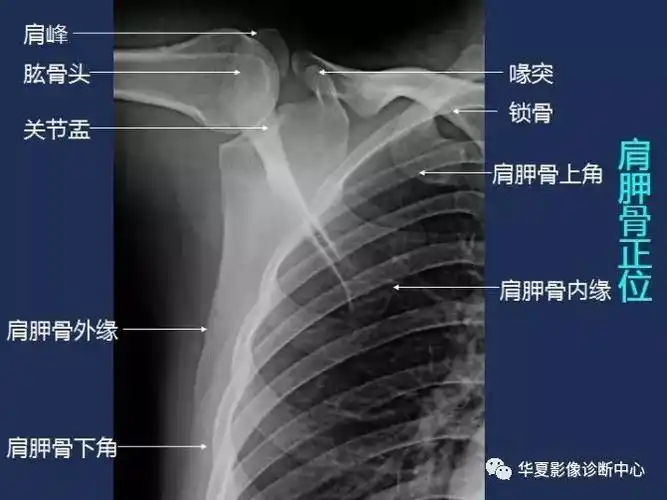

骨科常见疾病x线解析之肩部损伤

左肩x线片

x线解剖图谱肩胛骨

肩胛骨正侧位片与冈上肌出口位片投照要点*广东省中医院大学城运动